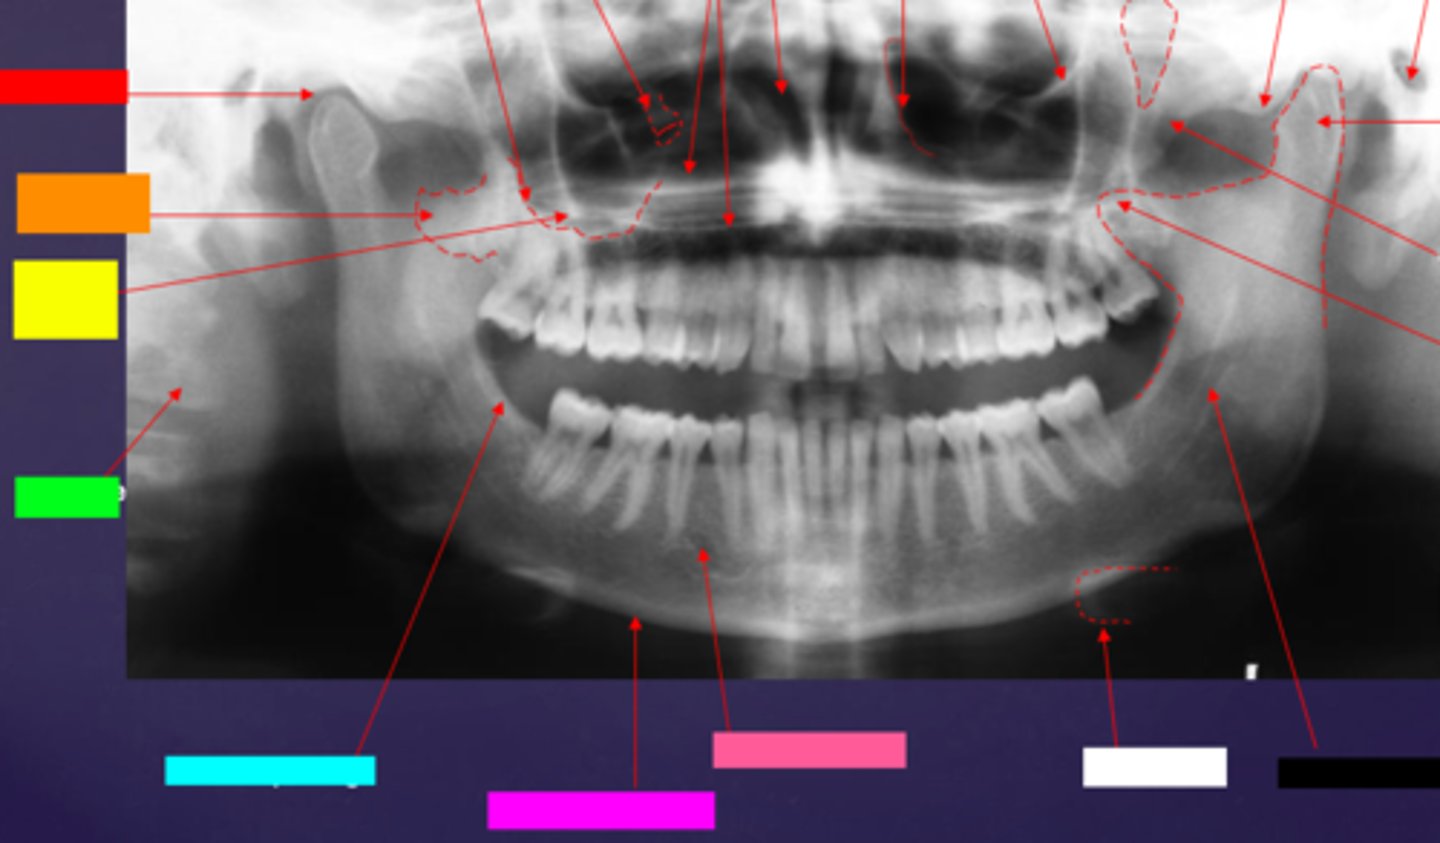

ID the hard tissue anatomy indicated by the arrow pointing from the red box:

mandibular fossa

ID the hard tissue anatomy indicated by the arrow pointing from the orange box:

lateral pterygoid plate

ID the hard tissue anatomy indicated by the arrow pointing from the yellow box:

zygomatic process of maxilla

ID the hard tissue anatomy indicated by the arrow pointing from the green box:

cervical spine

ID the hard tissue anatomy indicated by the arrow pointing from the light blue box:

external oblique ridge

ID the hard tissue anatomy indicated by the arrow pointing from the hot pink box:

inferior boarder of the mandible

ID the hard tissue anatomy indicated by the arrow pointing from the pink/salmon box:

mental foramen

ID the hard tissue anatomy indicated by the arrow pointing from the black box:

inferior alveolar canal

ID the hard tissue anatomy indicated by the arrow pointing from the white box:

hyoid bone